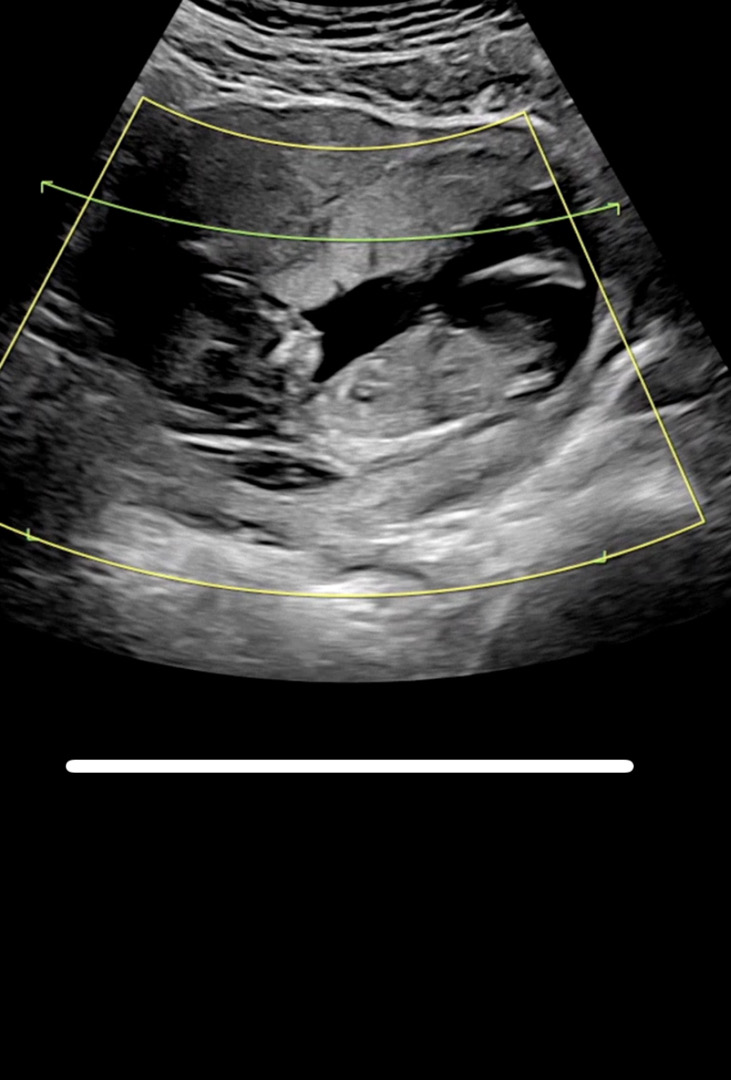

12주차 각도법좀 봐주세요 ㅠㅠ

부탁드립니다 ㅠㅠ